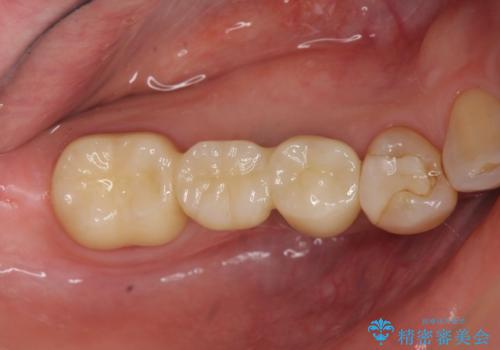

- 「数年前に入れたブリッジがぐらぐらする、診て欲しい。」と来院されました。

ブリッジを支える歯が割れてしまい、抜歯が必要であることと、骨の大きな吸収が見られました。

今回はインプラント埋入時に固定が得られたので同時に骨の造成を行い治療を進めることができました。